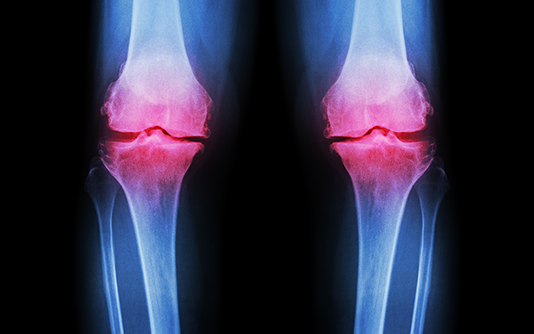

Nos articulations jouent un rôle dans tout ce que nous faisons et dans chaque mouvement que nous effectuons. Lorsque l’arthrite cause de la douleur, de la raideur et de l’enflure articulaire, nous pouvons nous sentir paralysés. Prendre soin de nos articulations et les bouger de façon appropriée est la priorité numéro un de tout plan de traitement de l’arthrite.